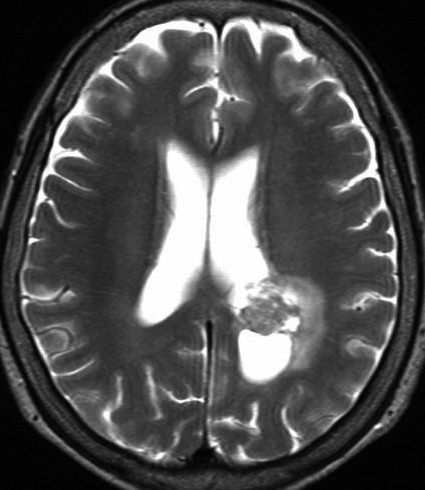

思春期に難治性てんかんで発症した典型例 occult PXA?

7歳児に頭痛に嘔気を伴う,1分間くらいの短い発作で発症しました。

左は8歳時のMRIで,異常所見がありませんでした。左側頭葉に発作時の異常脳波所見が認められ,側頭葉てんかんの診断でカルバマゼピンの投与が開始されました。9歳時に精神症状を呈する発作となりレベチラセタムとゾニザミドが加えられました。右側のMRIは9歳時のものですが異常所見はありませんでした。前後にさまざまな画像が撮影されていましたが脳腫瘍の所見はありませんでした。

11歳時のMRIで側頭葉下面に異常所見が出現しました。

カルバマゼピン,ガバペンチン,ゾニザミド,ラコサミド,クロバザムの5剤投与を受けていましたが発作は制御できませんでした。

12歳時,私のところへ来た時のガドリニウム増強像です。開頭手術で扁桃体を含めて全摘出してから発作は止まり,術後3年で抗てんかん薬は中断できています。